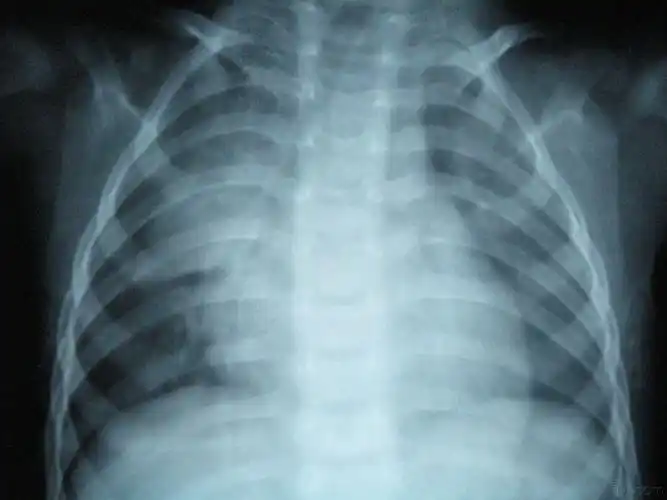

这几组患儿胸片是肺炎还是正常影像规培医师懵了